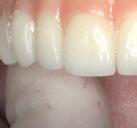

Este último aparato funcional se mantuvo en boca durante 8 meses, tras haber conseguido la mejoría esperada en cuanto al aspecto facial (figura 17) y las relaciones oclusales (figuras 18 a 22). La mordida abierta lateral producida es fácilmente solucionable en la siguiente fase de tratamiento.

Con el cementado de los brackets de la técnica Universal Smile System

(USS), como se aprecia en las figuras 23 a 25, comienza la segunda fase de tratamiento. Esta duró tan solo 12 meses debido a que gran parte de las relaciones oclusales habían mejorado durante la etapa anterior. Los resultados finales del tratamiento se observan en las figuras 26 a 30 , con la corrección de la clase molar y canina, el resalte y la sobremordida, el centrado de las líneas 1/2 y la curva de Spee. La mejoría en la macro, mini y microestética facial se aprecia en las figuras 31 a 33 , a pesar de la evidente desviación del mentón hacia